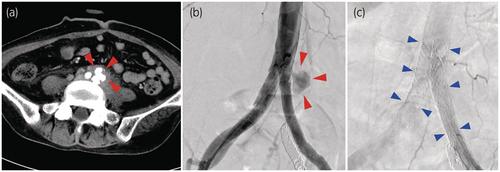

A 38-year-old woman with radiation-induced vesicovaginal fistula and bilateral ureteral stenosis underwent urinary diversion using an ileal conduit. During left ureteral stent exchange, a ureteroarterial fistula occurred on the left side and was successfully treated with vascular stent grafting. One year later, gross hematuria recurred, requiring open surgical intervention because of the formation of an infectious pseudoaneurysm near the aortic bifurcation.